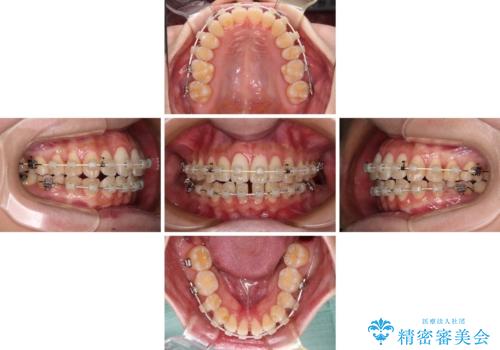

- 審美装置

- 3年

当初は上記計画でしたが、レントゲン撮影よりインプラント埋入は困難と判断され、患者様と相談の上、歯を削ってブリッジとするよりも、奥歯の咬み合わせを多少妥協することとなっても、スペースを閉じて仕上げていくこととしました。

1年弱で治療方針を変更したため、治療期間は長くなりましたが、スペースは無事に閉じ、咬合の違和感なく仕上げることができました。